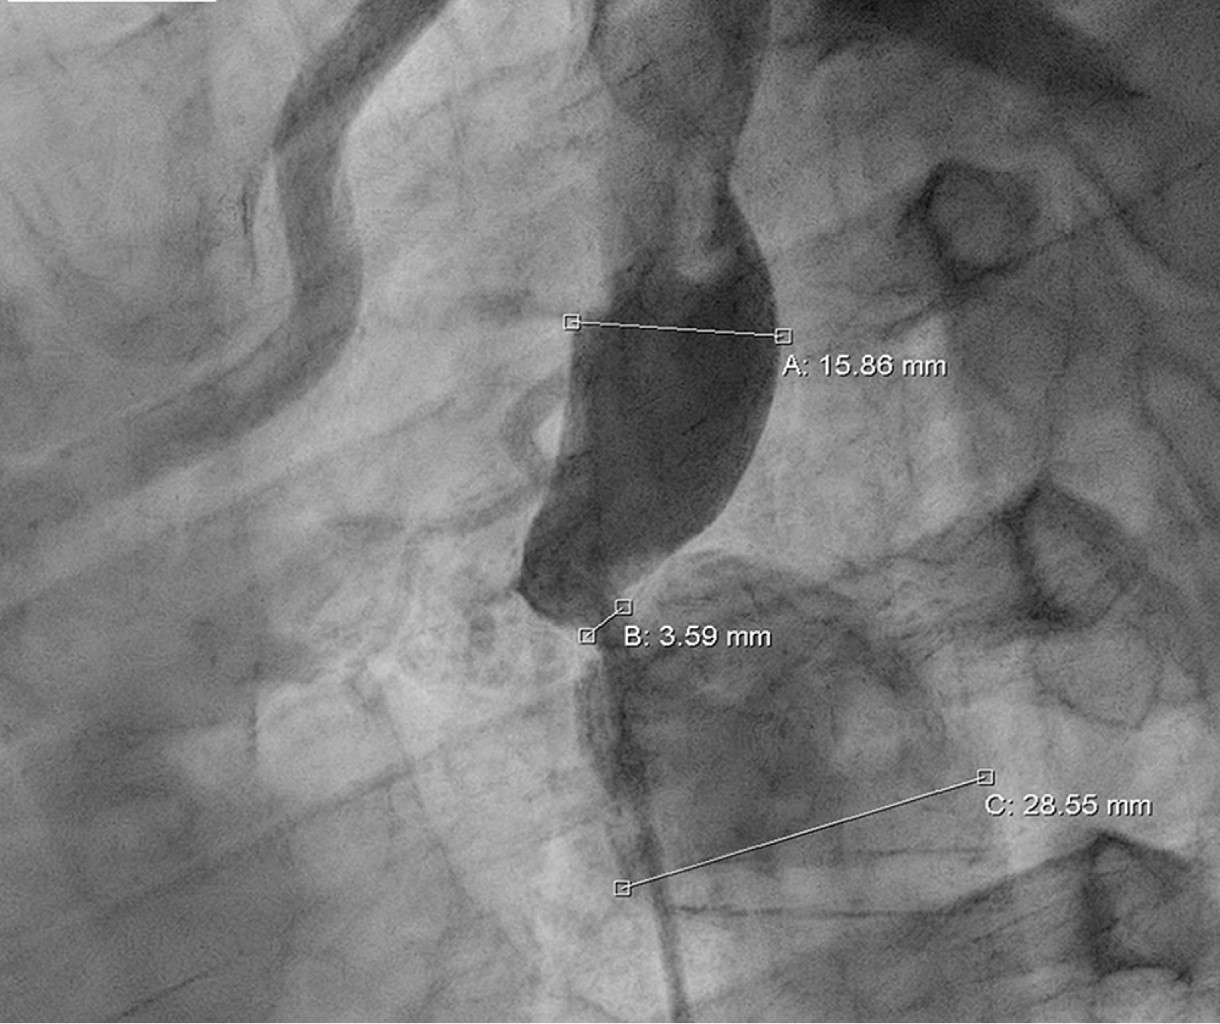

Coartación aórtica asociada a válvula aórtica bicúspide complicada con aneurisma aórtico postdisección

Sánchez-Amaya DJ, Godínez-Córdova LB, López-Lizárraga MÁ, Araiza-Garaygordobil D, Arias-Mendoza A

coartación aórtica, disección aórtica crónica, aneurisma aorta ascendente, válvula aórtica bicúspide.

La coartación aórtica es un trastorno congénito que afecta no solamente a la aorta, sino que también puede asociarse a válvula aórtica bicúspide y predispone a síndromes aórticos. Se reporta el caso de un paciente de 28 años de edad con hipertensión secundaria debido a coartación aórtica postductal asociada a válvula aórtica bicúspide que a su vez presentó disección crónica de la aorta ascendente. La coexistencia de enfermedad valvular aórtica, así como múltiples condiciones aórticas, es una situación rara que requiere una evaluación altamente especializada para garantizar un resultado favorable. El tratamiento se estableció en dos fases: aortoplastia con colocación de stent y luego cirugía de reemplazo aórtico y valvular, con una recuperación favorable.

Figura 2